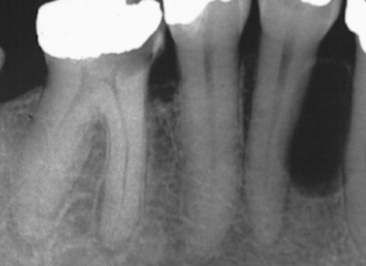

Describe this Radicular Cyst

Epicenter at apex (usually evidence of dental disease or trauma)

Well-defined, corticated

Lucent

Circular

Resorption, Displacement, Expansion (effect on adjacent structures)

Why is this Radicular cyst less circular/oval in this case?